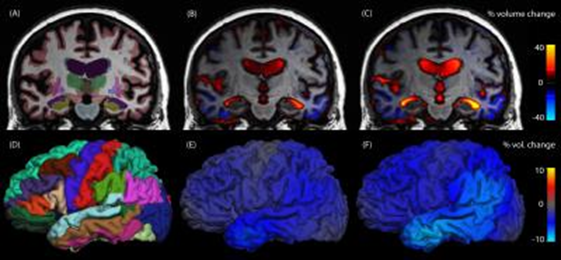

Developments in neuroscience are repeatedly demonstrating the phenomenal plasticity of the human brain. Studies such as; Neuroplasticity: Changes in grey matter induced by training by Draganski et al, have shown that mentally stimulating training induces selective structural changes within the brain. These changes in turn improve the mental processing associated with a particular skills or ability.